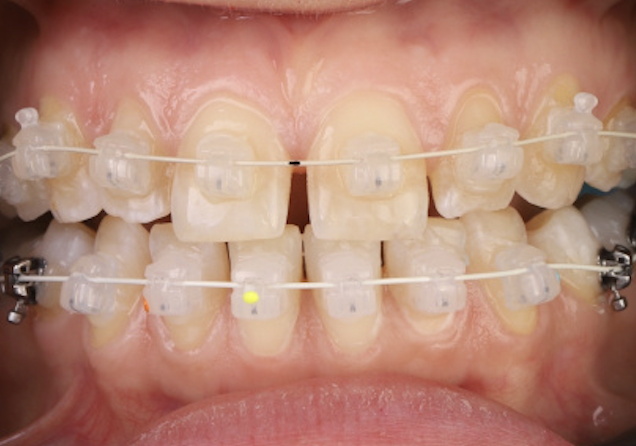

실제 치료 사례

데이몬 교정으로 완성된 아름다운 변화를 확인하세요

비발치 데이몬 교정

치아를 뽑지 않고도 완벽한 치열 개선

돌출 개선 + 얼굴윤곽 변화

자연스러운 치아 이동으로 얼굴형까지 개선